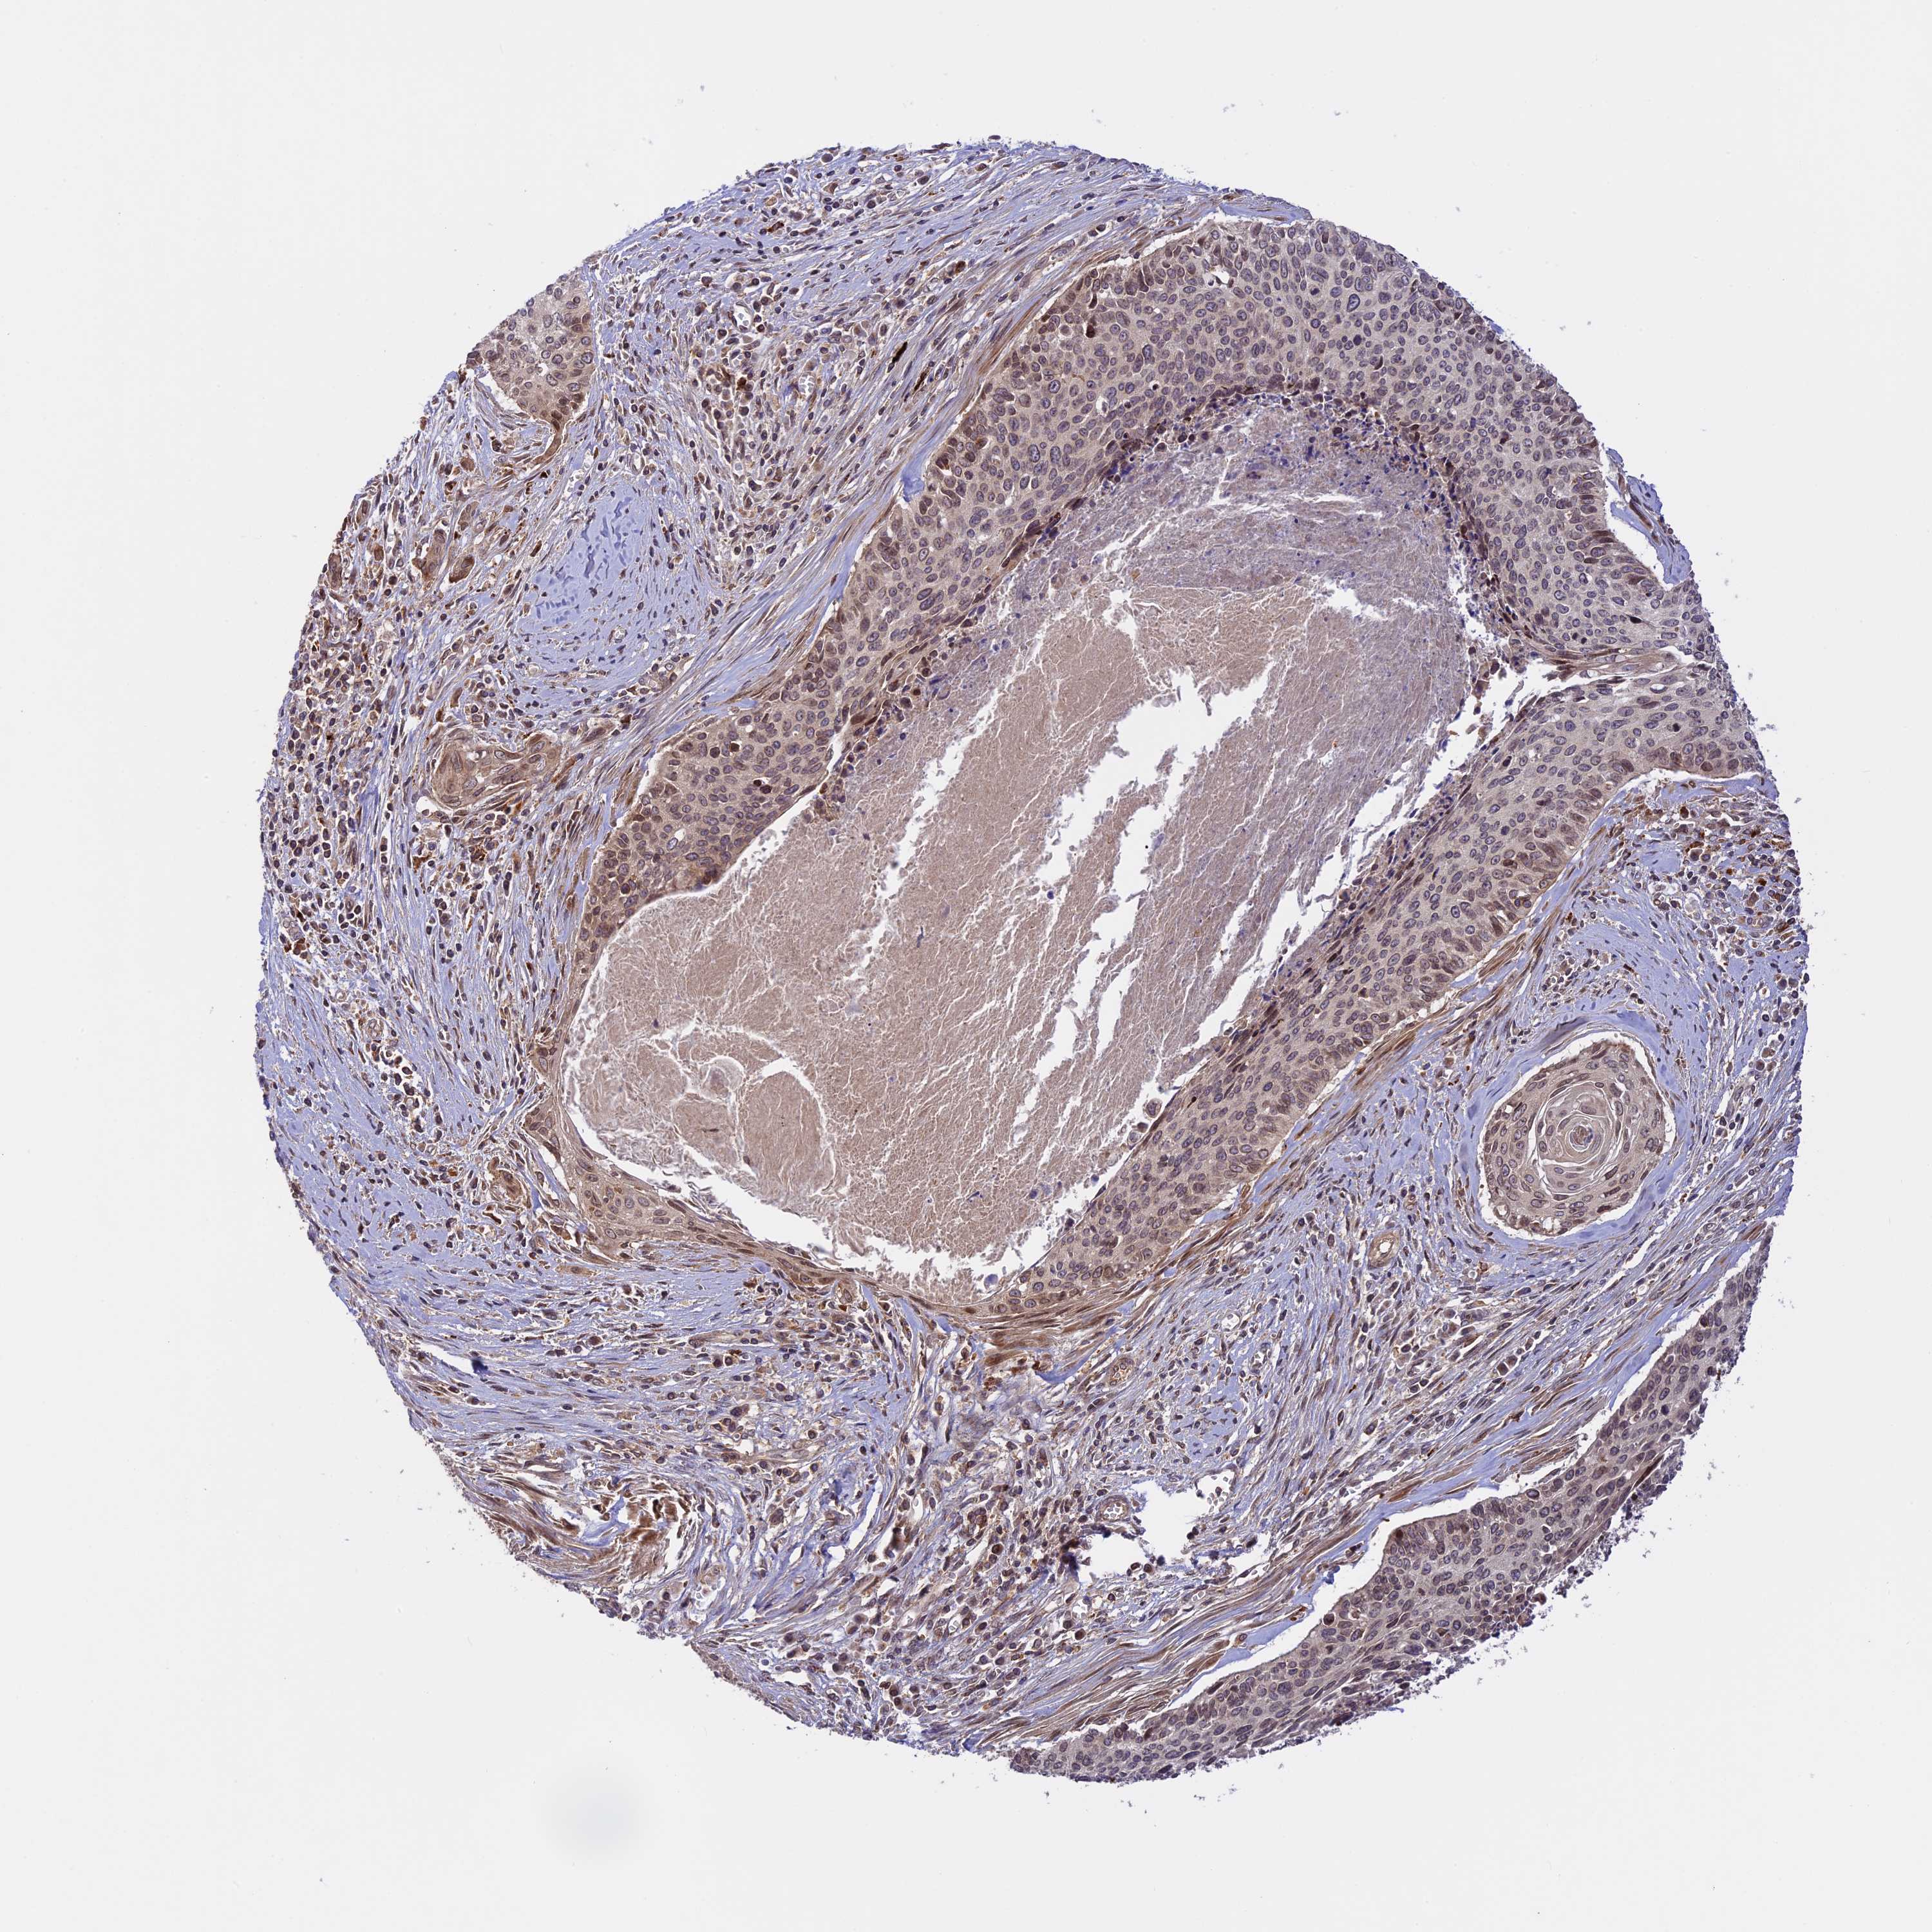

CERVICAL CANCER - Protein expressioni

A mouse-over function shows sample information and annotation data. Click on an image to view it in a full screen mode. Samples can be filtered based on level of antibody staining by selecting one or several of the following categories: high, medium, low and not detected. The assay and annotation is described here.

Note that samples used for immunohistochemistry by the Human Protein Atlas do not correspond to samples in the TCGA dataset.

Antibody stainingi

Antibody staining in the annotated cell types in the current human tissue is reported as not detected, low, medium, or high, based on conventional immunohistochemistry profiling in selected tissues. This score is based on the combination of the staining intensity and fraction of stained cells.

Each image is clickable and will lead to virtual microscopy that enables deeper exploration of all samples and also displays staining intensity scores, fraction scores and subcellular localization as well as patient and tissue information for each sample.

Antibody HPA039533

Antibody HPA040355

Squamous cell carcinoma, NOS

Adenocarcinoma, NOS